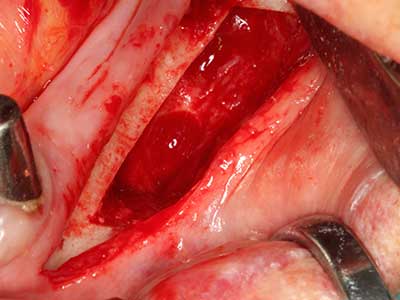

Piezo surgery has additional advantages when harvesting bone blocks. In addition to the high precision with osteotomy described above, the use of the thin saw tips specifically minimizes loss of material. Greater loss of material during harvesting can be expected with the thicker instrument tips, particularly when using Lindemann drills (Lakshmiganthan, Gokulanathan et al. 2012). The basal separation, which is necessary particularly for retromolar block transplants, is simplified by specially designed rectangular saws, with the result that piezo surgery is viewed as a precise, simple and safe procedure for harvesting retromolar bone blocks (Happe 2007) (Fig. 1-12).

Fig. 1: Preparation of a bone cover with the Piezomed (W&H Salzburg, Austria).

Fig. 3: Basal separation of the block is easier with specially angled attachments.